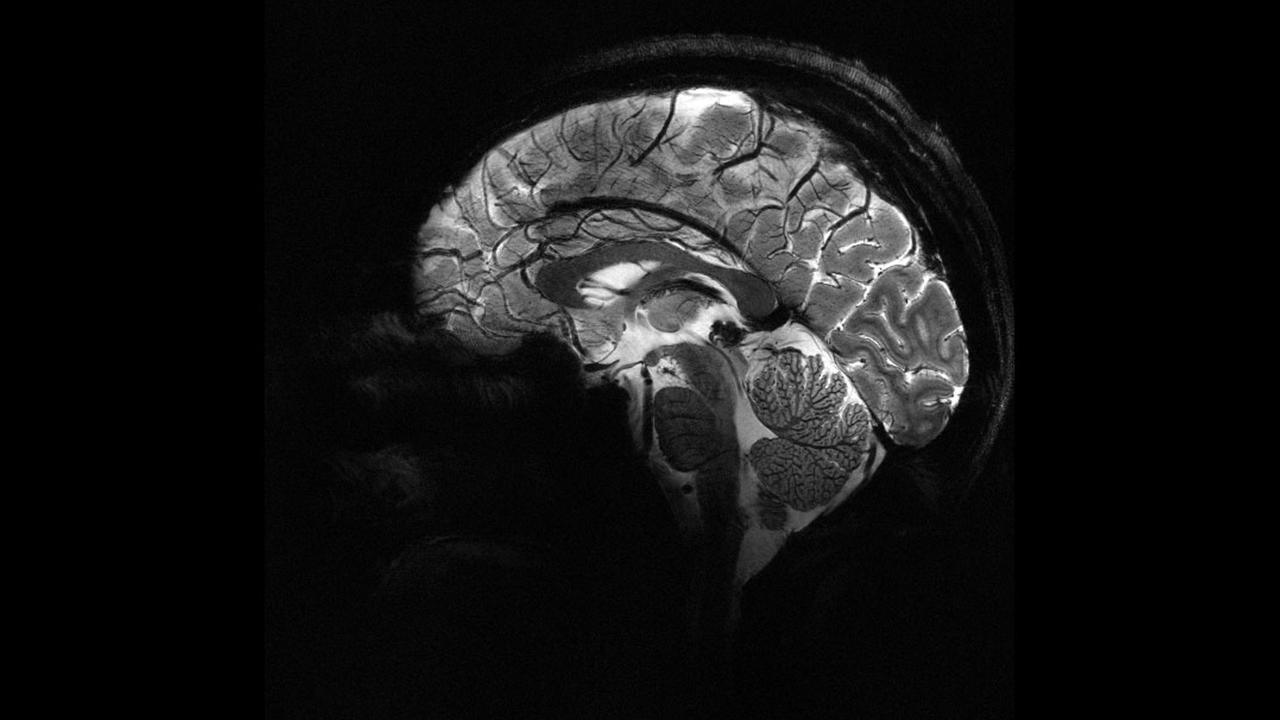

Pandemi beyinleri hızla yaşlandırdı

Nottingham Üniversitesi’nden bilim insanları, UK Biobank’ta yer alan 15 binden fazla yetişkinin verileriyle sağlıklı beyin yaşlanmasını tanıyan bir yapay zekâ modeli geliştirdi. Model, pandemiden önce tarananlarla, önce ve pandemi sırasında taranan iki grubun beyin yaşlarını karşılaştırdı.

Araştırmaya göre, pandemi sürecinde insan beyninin yaşlanma hızı ortalama 5,5 ay öne çekildi.